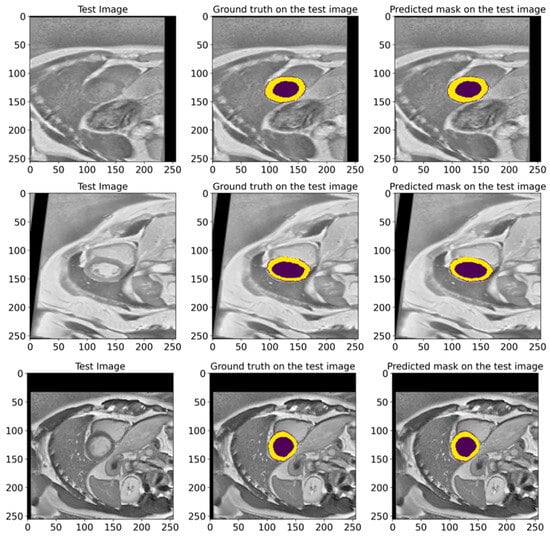

Figure 9 illustrates various examples from the test dataset with the corresponding actual masks generated by the experts and the predicted masks produced by our model. Examples demonstrate the segmentation accuracy of the model. A comparison of the actual and predicted masks shows that the proposed model successfully identifies the significant structures of the cardiac region, including the left ventricle and myocardium. The model demonstrates a high accuracy even in complex cases where the boundaries of the structures are less clear. These visual results confirm the effectiveness of the developed pre-processing methods and model architecture in improving the quality of the automatic segmentation of medical images. Our proposed heart segmentation model based on deep neural networks and image enhancement demonstrated a high efficiency and accuracy. It confirms its potential for use in clinical practice and contributes to improving methods for diagnosing cardiovascular diseases.

Figure 9.

Representative examples from the EMIDEC test set, showing the GT masks and the corresponding predictions made by our model. The deep violet areas represent the LV, while the yellow areas correspond to the Myo.